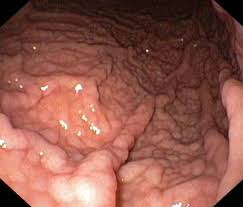

குடல் புண் இருப்பதாக தோன்றினால் வாய் வழியாக் குழாய் செலுத்தி செய்யப்படும் எண்டோஸ் கோப்பி பரிசோதனை மூலம் திசு மாதிரி எடுத்து (பயாப்ஸி) சோதனைசெய்து அது எந்த மாதியான புண் என உறுதி ப் படுத்திக்கொண்டு அதற் கேற்ற சிகிட்சை செய்வது ‘நல்லது.